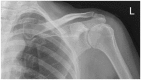

Figure 1.

A normal anteroposterior radiograph of the patient's left shoulder (5 weeks after vaccination).